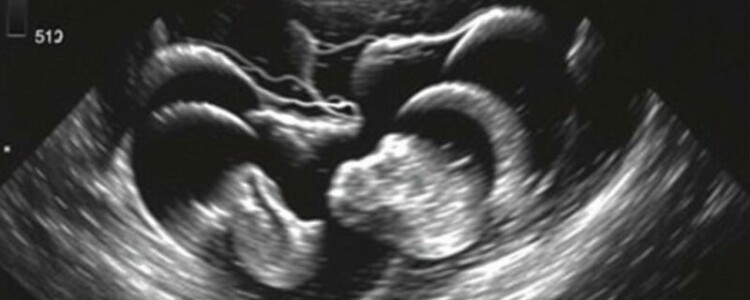

Particularidades en pediatría y en la mujer en edad fértil

En niños, la ecografía es la prueba de elección por evitar radiación. Los niños suelen tener apéndices más superficiales y mejor visualizables con transductores lineales. Sin embargo, la cooperación puede ser limitada y en los lactantes o niños pequeños la técnica exige experiencia. En mujeres en edad fértil, es imprescindible distinguir la patología apendicular de la ginecológica: torsión ovárica, enfermedad inflamatoria pélvica, quistes hemorrágicos, y embarazos ectópicos pueden presentar imágenes que se superponen con apendicitis. Un examen ecográfico transvaginal puede ser complementario y la colaboración con el equipo ginecológico es clave.

Recomendaciones prácticas para estos grupos

- Niños: usar transductor de alta frecuencia, paciencia para la compresión gradual, y si es posible realizar la exploración con los padres presentes para disminuir ansiedad.

- Mujeres en edad fértil: realizar también estudio ginecológico (transvaginal si indicado) y correlacionar pruebas de embarazo antes de considerar TC.